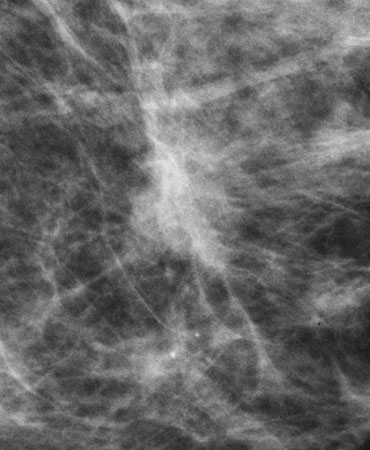

Stereotactic Core Biopsy Histopathology

Stereotactic Core Biopsy Histopathology:

Infiltrating carcinoma, duct cell type and intraductal carcinoma, cribriform type Grade II.

High power view histopathology (H & E)

High power view histopathology (H & E) shows high-grade intraductal carcinoma (DCIS).